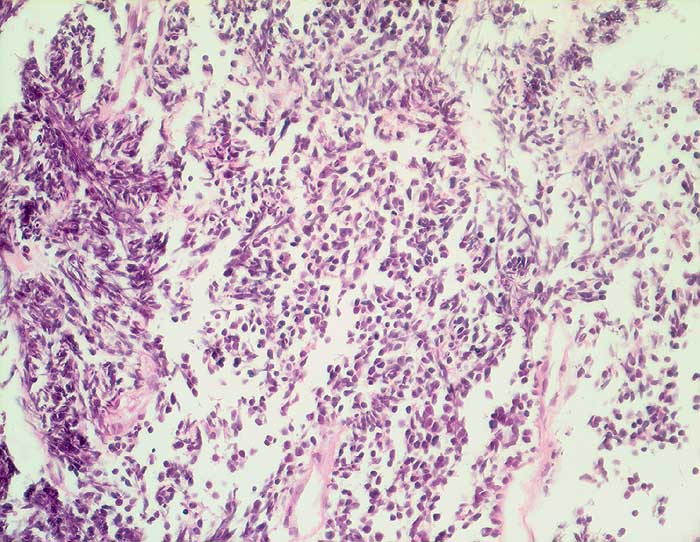

Kleinzelliges Karzinom

Rasen kleiner nacktkerniger Tumorzellen mit ausgeprägten Quetschartefakten aufgrund fragiler Kerne.

Tumor im Lungenmittellappen